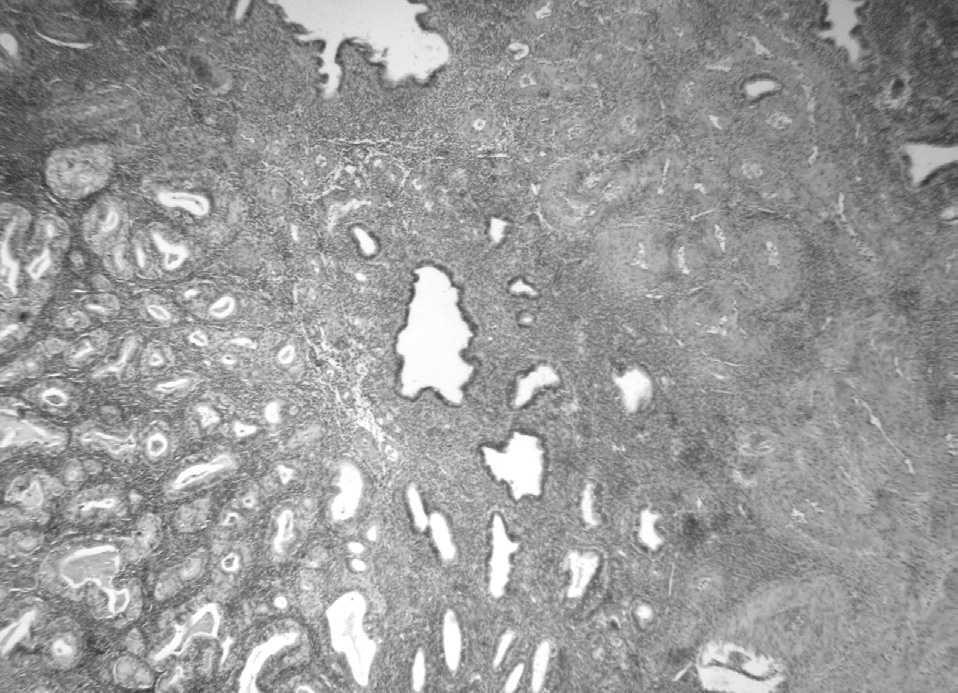

En 4 pacientes el diagnóstico de pólipo con adenocarcinoma se efectuó en una biopsia y en las otras 2 en la pieza de histerectomía, pues en ambas la biopsia previa reveló un adenocarcinoma sin criterios morfológicos de pólipo (tabla 2). El tipo histológico fue siempre endometrioide, y en el caso 1 se apreciaban focalmente algunas áreas serosas. El grado histológico según la FIGO fue G1 en 4 casos y G2 en los 2 restantes. El tamaño medio de los pólipos fue de 2,6 ± 1,7 cm (rango: 0,8-2,6) y en todos ellos la afectación por parte del adenocarcinoma era parcial; es decir, siempre se identificaron áreas de pólipo endometrial convencional conservadas. El tamaño medio de las neoplasias fue de 1,5 ± 0,6 cm (rango: 0,3-2). El cáncer se localizaba en la periferia del pólipo en 4 casos (fig. 1) y en la región central en 2 (fig. 2). En uno de los 2 casos en los que la lesión se encontraba en la porción central del pólipo existía afectación neoplásica del margen de resección. Sólo en uno de los casos se constató permeación tumoral de vasos linfáticos del pólipo.

Figura 2. Adenocarcinoma endometrioide en la región central de un pólipo endometrial (caso 2).